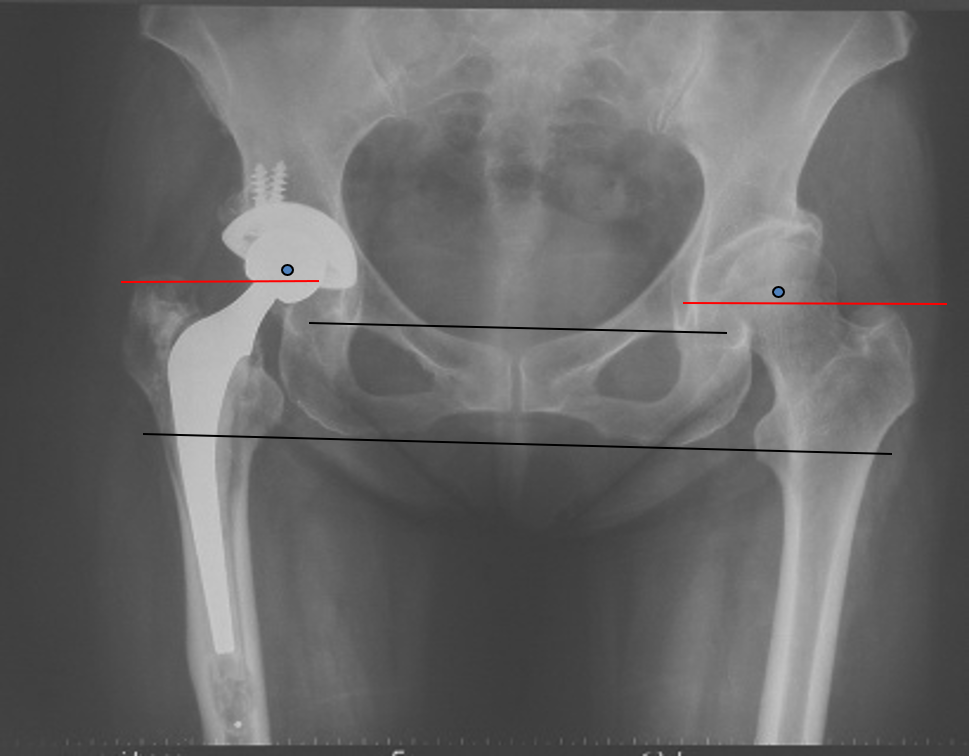

确定正常侧髋关节的旋转中心镜像至患侧:

单看股骨侧,大转子顶点和股骨头旋转中心的关系恢复了

但髋臼旋转中心点上移了造成了患肢术后肢体短缩因此如果术中发现髋臼旋转中心点有上移或下移,股骨假体也应相应的吊高或下沉以获得双下肢等长

术后股骨头旋转中心点增高,导致患肢延长